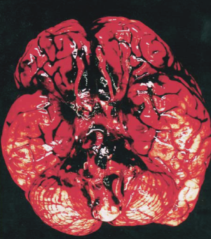

动脉瘤破裂导致脑组织表面广泛蛛网膜下腔出血

颅内动脉瘤如果体积较小,没有破裂,通常不会有明显症状;如果体积较大,可能会压迫周围的血管、神经,造成脑缺血症状和神经压迫症状,比如头痛、头晕、眼睑下垂、视物模糊、半侧脸麻木等。